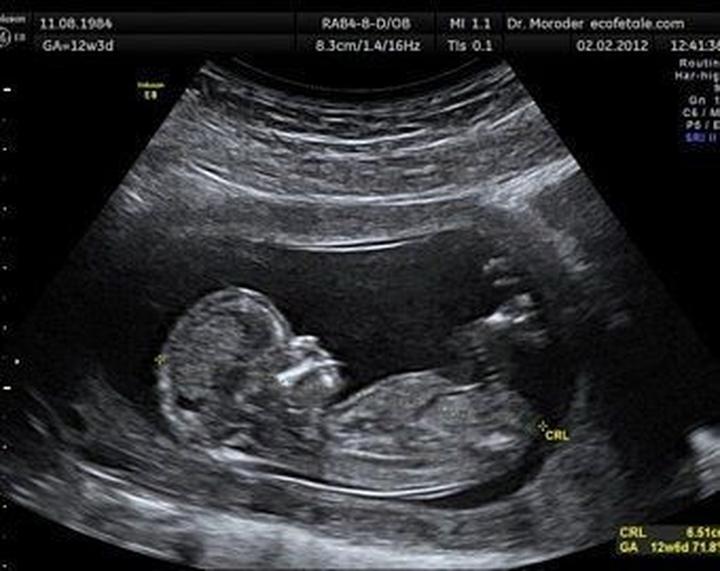

W trakcie badania lekarz stara się zmierzyć różne parametry, które stanowią cenne wskazówki dla przyszłych rodziców. Na przykład, CRL (długość ciemieniowo-siedzeniowa) to jeden z podstawowych wymiarów zarodka. Im większą wiedzę zdobędziesz, tym mniejsze prawdopodobieństwo, że później doświadczysz zaskoczenia jako „przerażony rodzic” z wynikiem USG w dłoni, na którym widnieją tajemnicze znaczki.

| CRL | Długość ciemieniowo-siedzeniowa | Podstawowy wymiar zarodka, który dostarcza informacji o jego rozwoju. |

Przechodząc do wyników badania, warto zmierzyć się z tajemniczymi skrótami, które mogą przyprawić o zawrót głowy. Co powiecie na GS, CRL czy NT? Te skróty zdają się bardziej przypominać kody z gier komputerowych niż wyniki USG. Dlatego dobrze jest uzbroić się w podstawową wiedzę: GS oznacza pęcherzyk ciążowy, CRL to długość ciemieniowo-siedzeniowa, a NT to przezierność karkowa. Już teraz można poczuć się pewniej w rozmowach z medykami, prawda?

Podczas badania USG w ciąży lekarz mierzy różne parametry, takie jak CRL (długość ciemieniowo-siedzeniowa), BPD (wymiar dwuciemieniowy główki) oraz FHR (częstość akcji serca płodu). Te dane dostarczają cennych informacji o rozwoju płodu oraz jego zdrowiu.